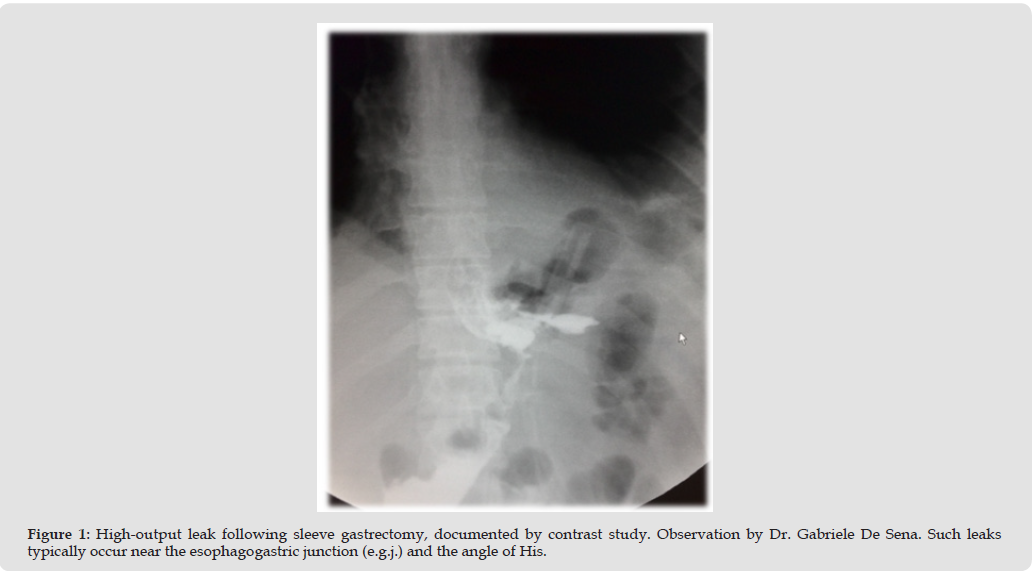

Bariatric surgery has become the most effective long-term treatment for morbid obesity and obesity-related comorbidities. However, postoperative leaks remain a dreaded complication, particularly after SG, due to the long staple line and high intraluminal pressure. Most leaks occur near the esophagogastric junction and the angle of His. Leaks are classified according to anatomy and timing. Management strategies have shifted from surgical revision toward less invasive endoscopic approaches. SEMS have represented the cornerstone of treatment for more than a decade. Their ability to cover large defects and restore enteral nutrition rapidly makes them an attractive option, particularly in unstable patients. However, growing experience with alternative modalities has led to debate regarding the continued role of SEMS in modern endoscopic practice.

SEMS remains an important tool in the endoscopic treatment of post-bariatric leaks, particularly in acute and early cases. They provide rapid control, facilitate nutrition, and can be combined with complementary therapies. However, their role in chronic or complex leaks is diminishing in favor of EVT, EID, or multimodal approaches. The optimal strategy is stepwise, patient-centered, and guided by a multidisciplinary team [1-9] (Figures 1- 5).